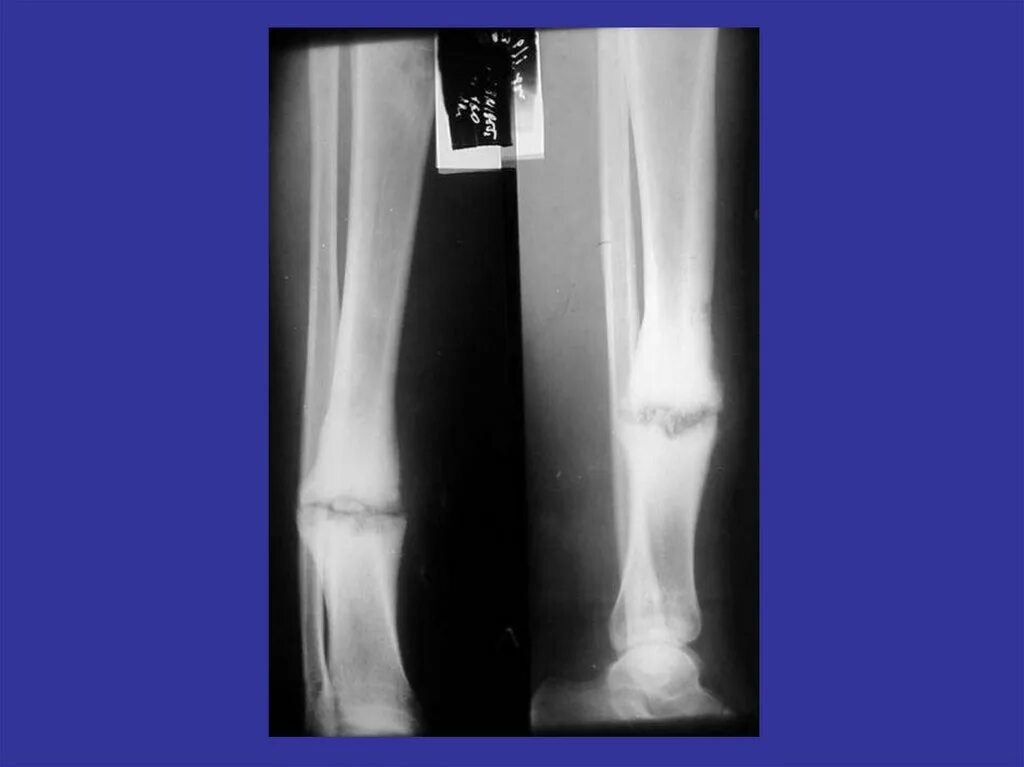

Не срастается сустав